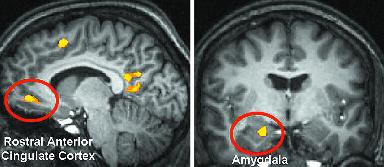

El núcleo accumbens, principal estructura cerebral que interviene en el proceso de duelo (imagen recuperada, de http://thebrain.mcgill.ca/flash/i/i_03/i_03_cr/i_03_cr_que/i_03_cr_que.html, el 23 de agosto de 2008)

Desde el proceso de inteligencia digital, se ha descubierto recientemente, una base científica para “alojar” (valga la expresión) el duelo, en su fase complicada, en el núcleo accumbens, al llevar a cabo un estudio comparativo entre el duelo no complicado y el complicado (3), utilizando imágenes de Resonancia Magnética Funcional: “Hasta ahora, poco se sabía de los mecanismos neurales que distinguen ambos tipos de duelo, explican los investigadores en la revista especializada Neuroimage [(4)], pero se habían considerado algunos mecanismos hipotéticos, como la actividad relacionada con el dolor (con la angustia social por la pérdida) y la actividad relacionada con la recompensa (con los comportamientos de apego). Una de las investigadoras, la doctora Mary-Frances O’Connor, declaró para la publicación de la UCLA que, en lo que se refiere al mecanismo de recompensa, la idea es que, mientras nuestros seres queridos están vivos, obtenemos señales gratificantes cuando los vemos o cuando vemos objetos que nos los recuerdan. Tras la muerte de un ser allegado, los que se adaptan a la pérdida dejan de obtener esta recompensa neural. Por el contrario, los que no consiguen adaptarse, continúan anhelándola, porque cada vez que ven una señal del ser querido aún obtienen la recompensa neural correspondiente. Todo este mecanismo sucede a nivel inconsciente, es decir que el doliente no pone en ello ninguna intención. El estudio se centró en analizar si las personas que sufren de duelo complicado presentan una mayor actividad tanto en el circuito de recompensa del cerebro como en el circuito del dolor. Para ello, fueron analizadas 23 mujeres que habían sufrido la pérdida de sus madres o de alguna hermana como consecuencia del cáncer de mama”.

El resultado ha ayudado a localizar bien la reacción cerebral ante imágenes de los seres queridos que han fallecido, activándose de forma sustancial el núcleo accumbens, es decir, se ha demostrado que el dolor crea adicción porque esta estructura se activa al visualizar o recordar a los seres que se querían y que han fallecido. Se necesita en definitiva este recuerdo porque es lo “único gratificante”, aunque “El estudio respalda por tanto la hipótesis de que los apegos activan los circuitos de recompensa y pueden por tanto convertirse en una interferencia para la adaptación a las pérdidas. Es decir que, aunque la activación del núcleo accumbens no satisfaga emocionalmente a los dolientes, señala O’Connor, se convierte en una respuesta que hace aún más difícil de superar la realidad del fallecimiento”. Y la adicción al dolor “puede llegar a generar el anhelo recurrente de emociones dolorosas como la ansiedad intensa o el deseo de morir. Ahora, este síndrome ha sido definido por un conjunto de criterios empíricos y se está considerando su inclusión en el Manual diagnóstico y estadístico de los trastornos mentales de la American Psychiatric Association (Asociación Psiquiátrica de Estados Unidos), el DSM-IV. Este manual consiste en una clasificación de los trastornos mentales con el propósito de proporcionar descripciones claras de éstos para facilitar sus diagnósticos”.

Ya sabemos la importancia de estos estudios de laboratorio con personas afectadas por procesos de duelo. El conjunto de neuronas que se recuestan cerca del sistema límbico, implicando la amígdala, el hipocampo y la corteza cerebral, se conoce como el “núcleo accumbens” (del verbo latino “accumbo”: recostarse, tenderse). Este núcleo cumple también una misión importante en el cerebro: obtener placer y mantenerlo el mayor tiempo posible, gracias a un neurotransmisor, la dopamina, que produce sentimientos y emociones de gozo como refuerzo ante determinados problemas que elabora la corteza prefrontal, con los que se encuentra en una experiencia tan traumática como la ocurrida en Barajas, llevándola a una proactividad encaminada a buscar continuamente actividades que permitan bienestar, bien-ser, en definitiva.